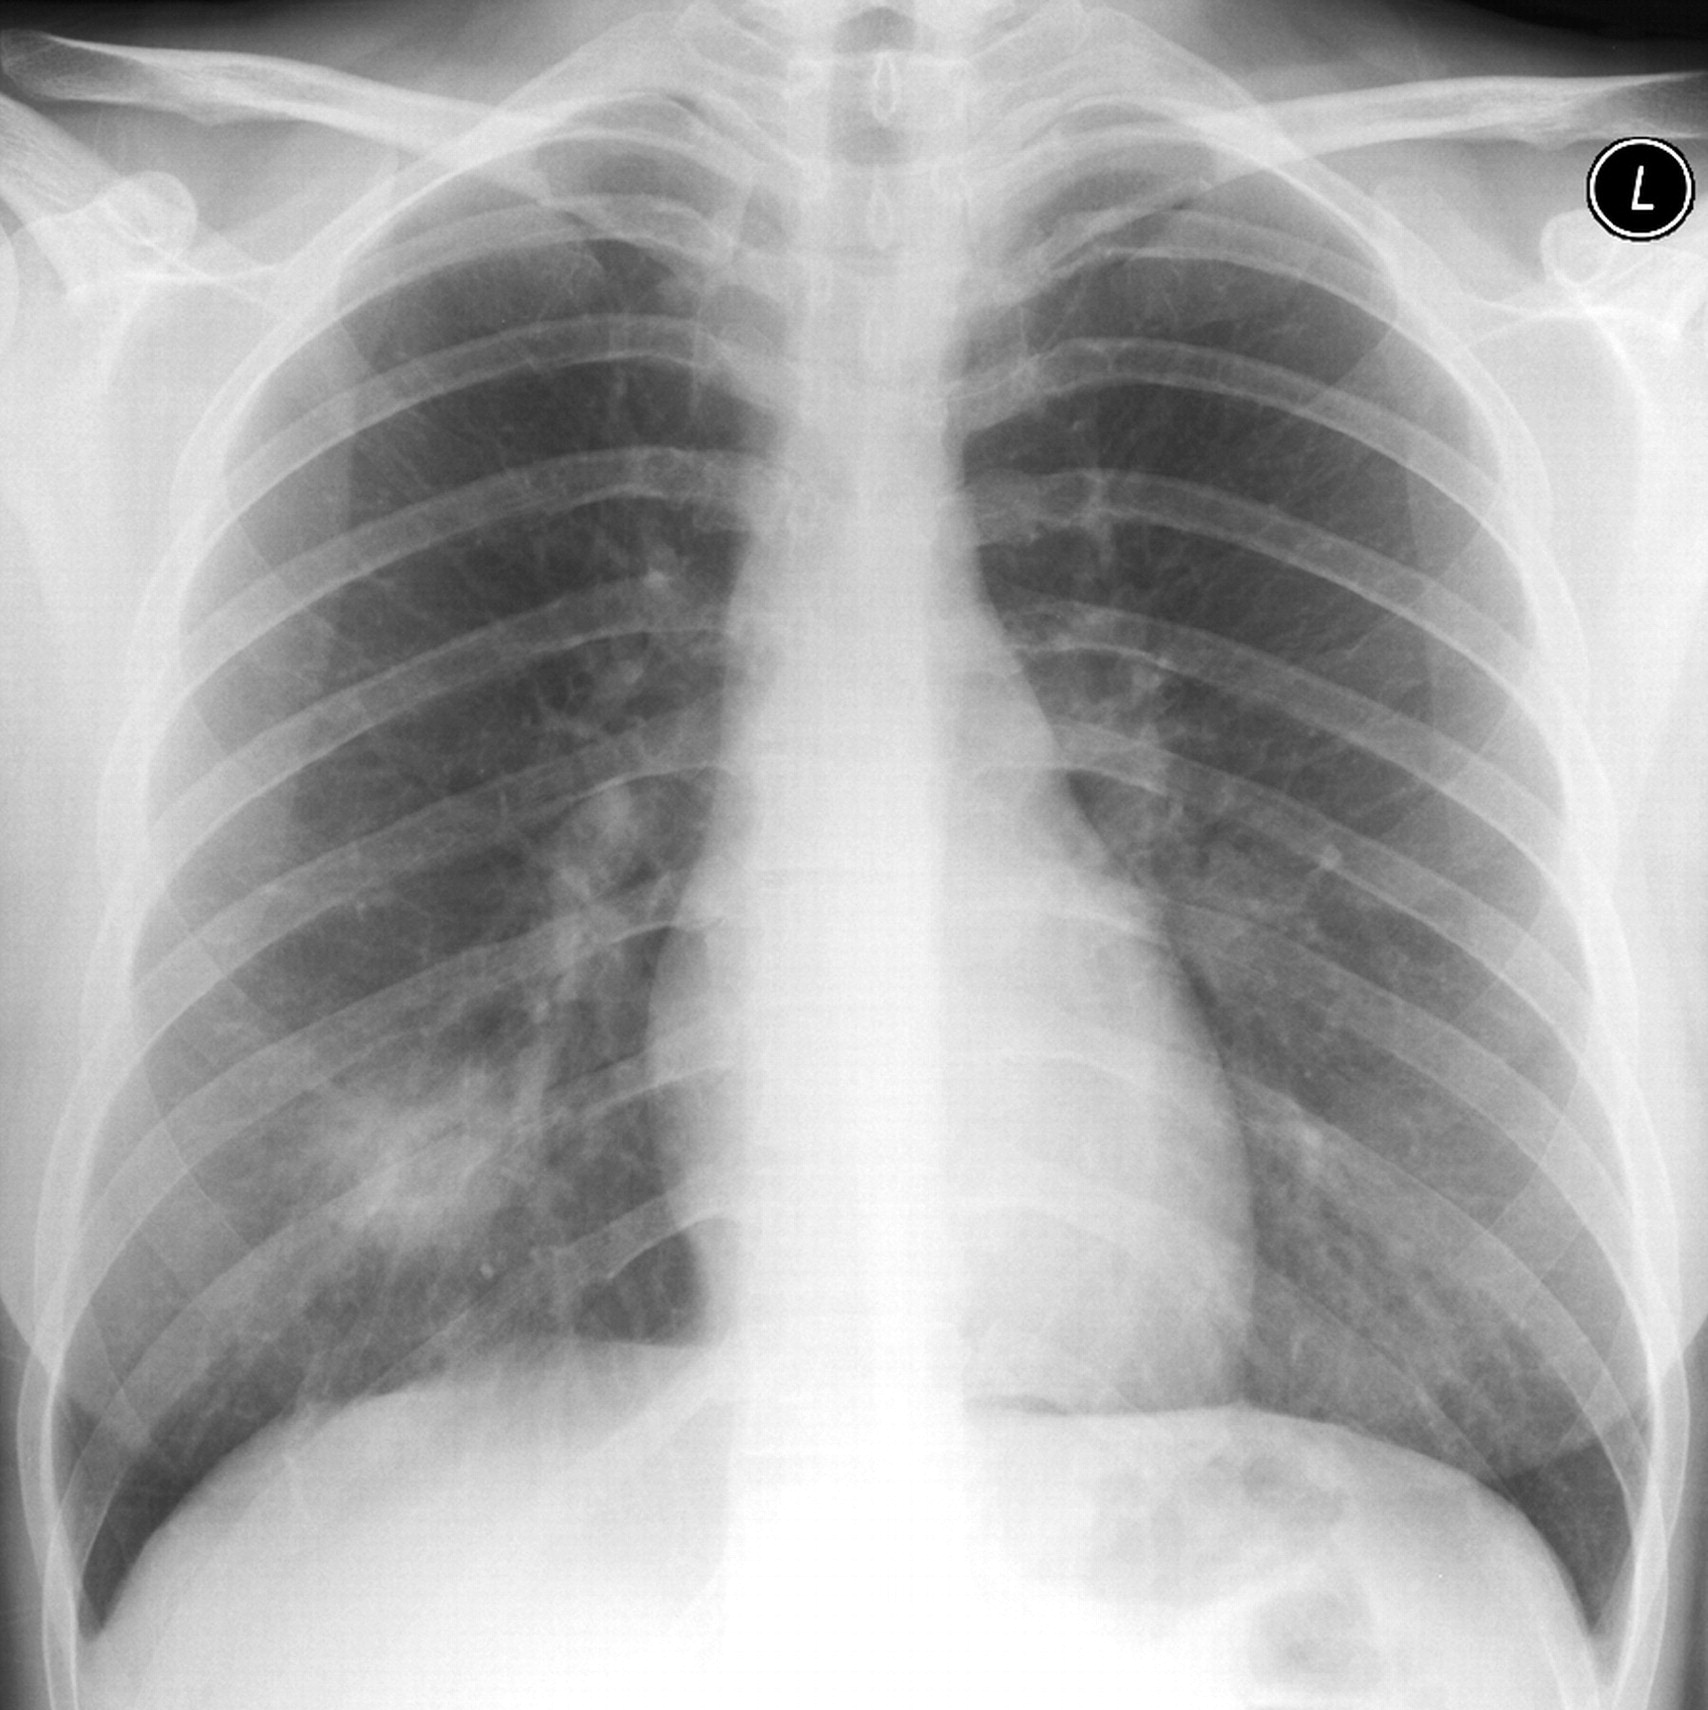

All our experiments use five-fold cross-validation to split target class. To compose the complete test set we use the fold used as a test, together with all the outliers samples. Finally, we repeat the approach twenty times taking means and variance to compare our results with other models. In our experiments we use six numerical datasets from UCI repository (see. Table. 5) and a novel dataset of Covid-19 that contains chest X-ray or CT images of positive/negative patients (see Fig. 1). In order to have the right comparison criterion in Covid-19 dataset, we extract confusion matrix as reported in Tab. 4 and compute the precision metric described in Eqs. 13 and 14. These last measures are needed to compare the class accuracy of the proposed OCdmst and the Resnet18 used in our experiments.

In the third experiment, we demonstrate by experimental results the effectiveness of our model with few data and compare it with a neural network (Resnet18). We simulate the scenario in which we have too few data to deny common neural networks to make right discrimination of different concepts (two classes in our case). Therefore we apply a 2-Fold cross-validation considering all data available from Covid-19 dataset and we extract the deep features for each model trained (Resnet18). All images have been re-scaled to 256x256 pixels and transformed to gray-scale. Learning rate and batch-size are set to 0.001 and 10 respectively. As evaluation metric we do not consider the total accuracy but we evaluate the accuracy for each class (Precision). Then, we use the deep features as input to our OCdmst using the dataset split in the previous step. The results reported in Tab. 2 show the flexibility of our model to operate also with

Resnet18 learned features using cross-entropy loss. As showed in Tab. 2, Resnet18 does not offer right prediction to recognize instances from negative class. This results is reasonable considering we have too few data with negative labels. Even when we used features extracted by Resnet18 to our model, but OCdmst is able to recognize value from both classes and overcome the right prediction also on positive class. The confusion matrix showed in Fig. 7 and accuracies for each class demonstrate the capability of OCdmst to operate also in a scenario with few data, as well as overcome deep neural networks. This last result is plausible because it represents one of the weaknesses of deep models.